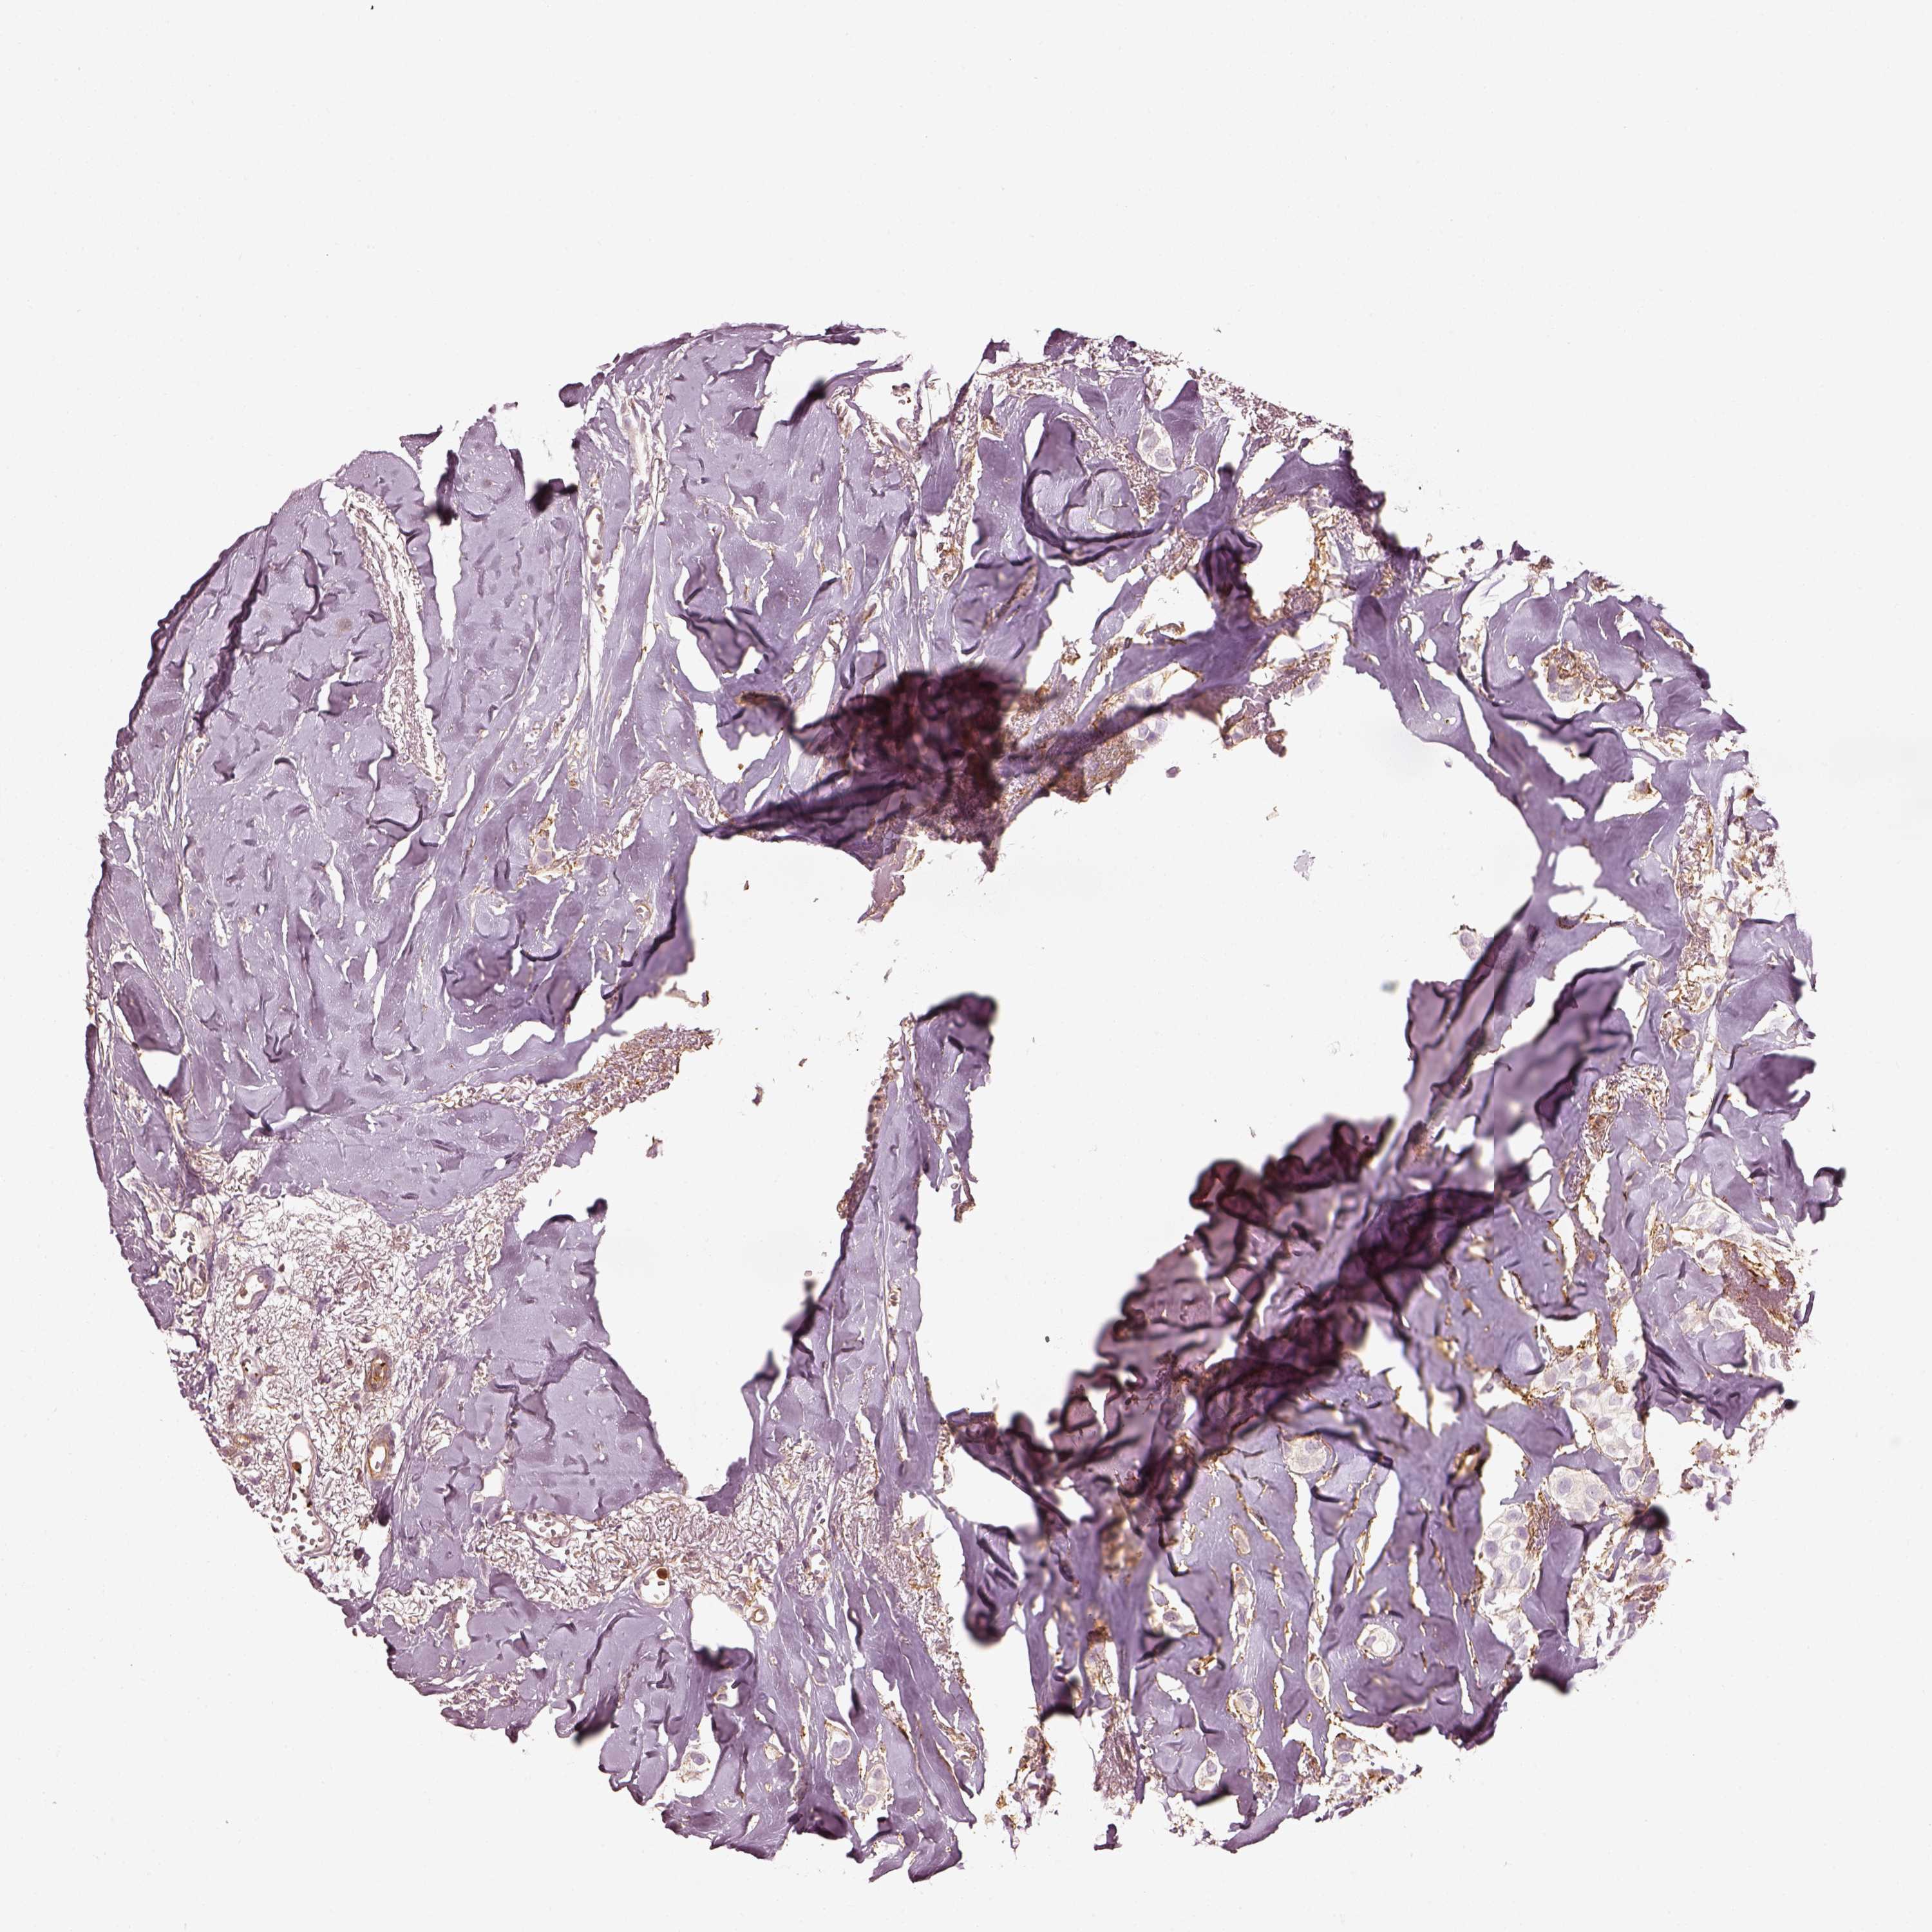

CANCER BREAST CANCER Show tissue menu

BRCA TCGA BRCA VALIDATION PROTEIN EXPRESSION